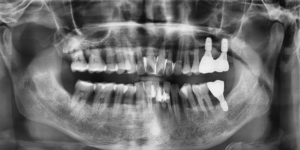

다만 왼쪽 위와 아래 어금니 치아는

동요도가 끝까지 남아 있어 발치가 불가피했고

해당 치아는 발치 즉시 임플란트 식립을 진행하며

치조골 이식술을 병행했습니다.

뼈가 많이 소실됐던 부위였기 때문에

골재생을 유도하는 과정이 중요했지만

발치 즉시 식립 후 경과는 매우 양호했습니다.

최종 보철 완성 후 촬영한 사진에서는

임플란트를 식립한 부위의 치조골이

안정적으로 재생된 모습을 확인할 수 있었고

환자분은 임플란트 포함 모든 치아를

불편함 없이 사용하고 계십니다.